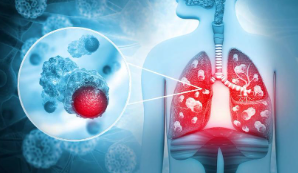

폐암 이란?

폐암은 말 그대로 폐에 생긴 악성종양을 의미합니다. 크게 소세포폐암과 비소세포폐암으로 나뉘는데, 대부분의 폐암환자분들은 비소세포폐암에 해당됩니다. 전체 폐암 중 80~85%가량 차지하며, 편평 상피세포암, 선암, 대세포암등이 속합니다.